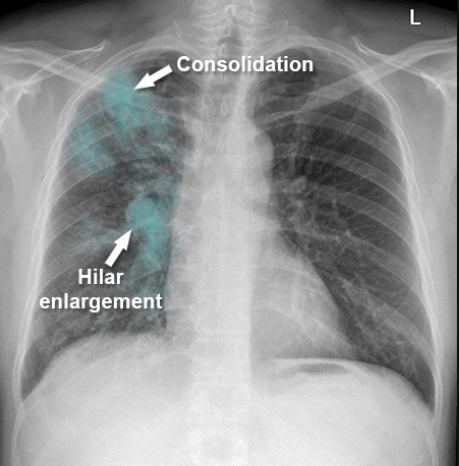

결핵 진단과 검사 방법

결핵 진단과 검사 방법: 피부반응 검사, 가슴 엑스레이, 가래침 검사 결핵은 결핵균(Mycobacterium tuberc...